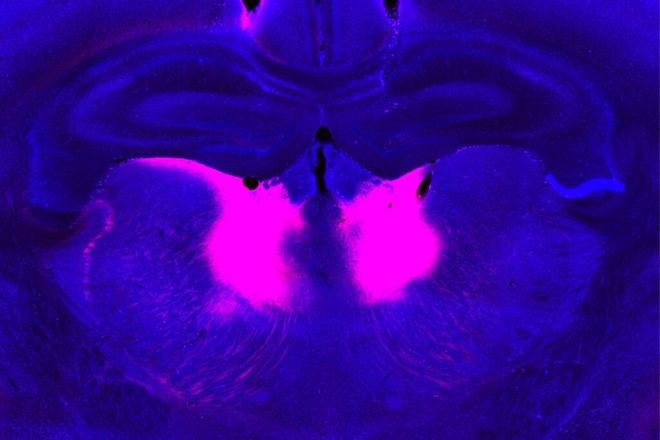

Identifican circuito cerebral relacionado con la esquizofrenia y la dificultad para integrar nueva información

Investigadores del MIT han identificado una mutación genética que afecta un circuito cerebral, lo que podría explicar las dificultades para incorporar nueva información en personas con esquizofrenia.

Científicos del MIT han identificado recientemente una mutación genética que parece estar relacionada con este tipo de dificultades. En un estudio realizado en ratones, los investigadores descubrieron que esta mutación afecta el funcionamiento de un circuito cerebral responsable de actualizar creencias basadas en nueva información.

En el nuevo estudio publicado en Nature Neuroscience, Feng y su equipo crearon un modelo murino con una mutación en uno de esos genes, grin2a. Este gen codifica una proteína que forma parte del receptor NMDA —un receptor activado por el neurotransmisor glutamato— comúnmente encontrado en la superficie de las neuronas.